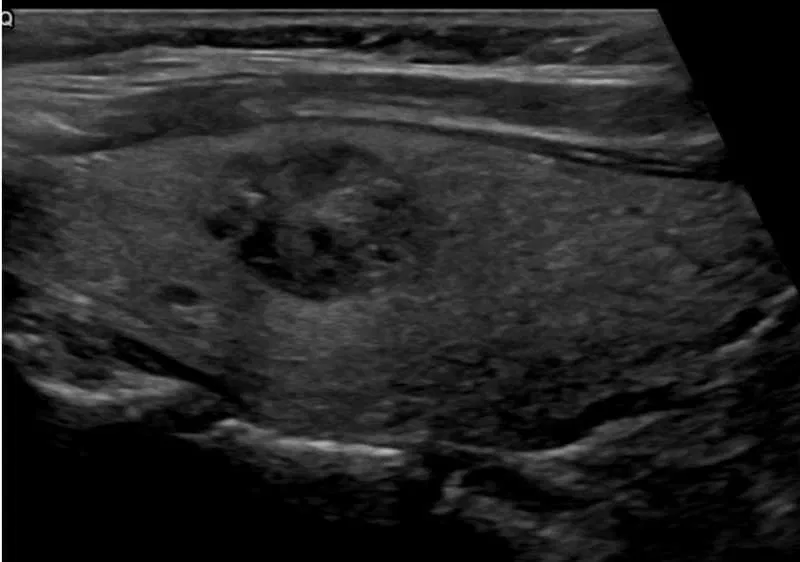

Example 3:

What is the TIRADS score for this nodule?

TIRADS example 3 RadioGyan.com

Answer:

1 point – Mixed cystic and solid

2 points – Hypoechoic

0 point – Shape: Wider than tall

0 point – Ill-defined margin

3 points – Punctate echogenic foci

Total 4, 5 0r 6 points = TIRADS 4 nodule; Risk of neoplasm <5%